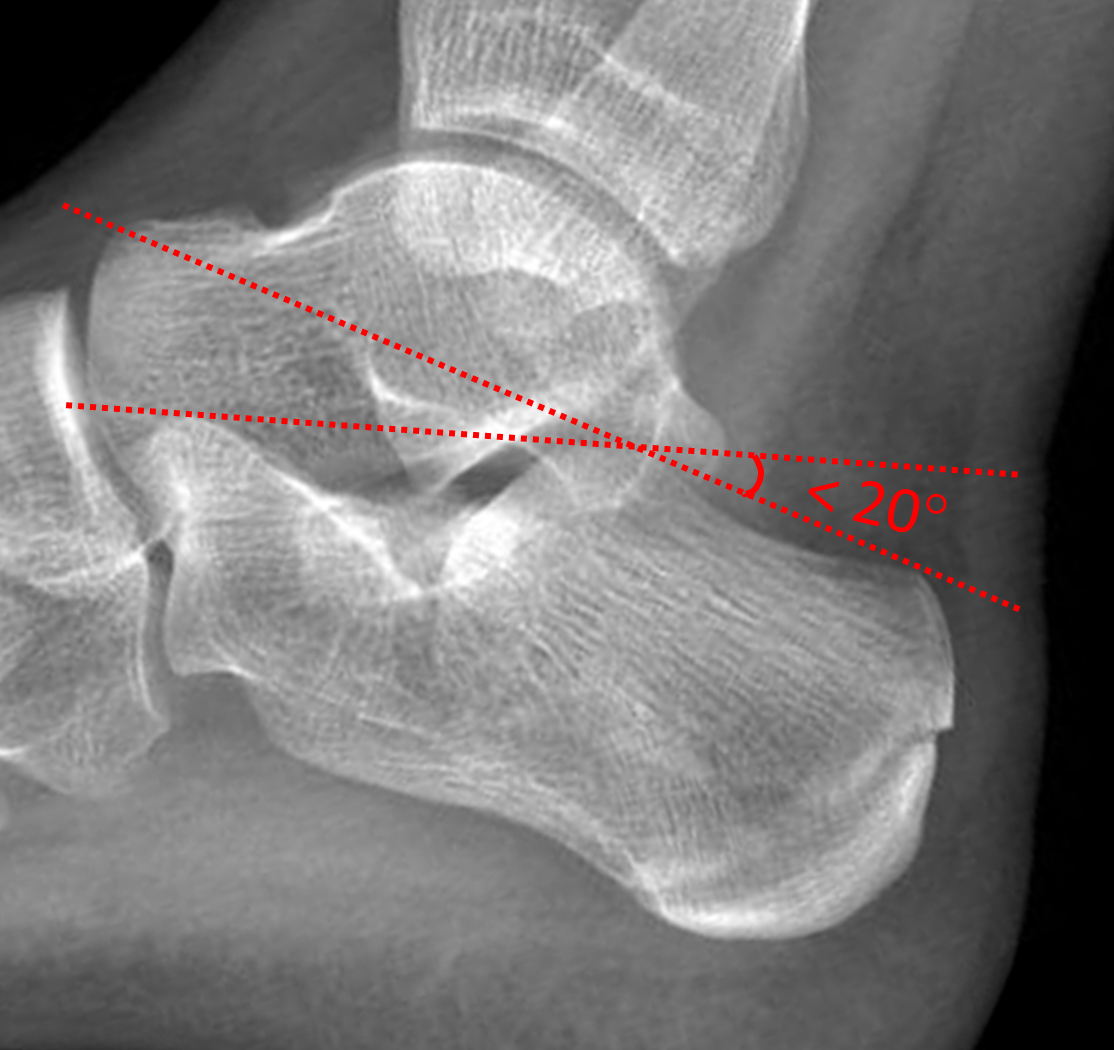

From mavink.com

Calcaneal Fracture Angle Boot For Calcaneal Fracture Calcaneus fractures are the most common fractured tarsal bone and are associated with a high degree of morbidity and disability. For those calcaneus fractures that are not displaced, treatment may involve the use of crutches and/or a protective boot or brace, or, plaster cast immobilization. We recommend the skechers max. Treatment for calcaneus fracture is decided based on the type. Boot For Calcaneal Fracture.